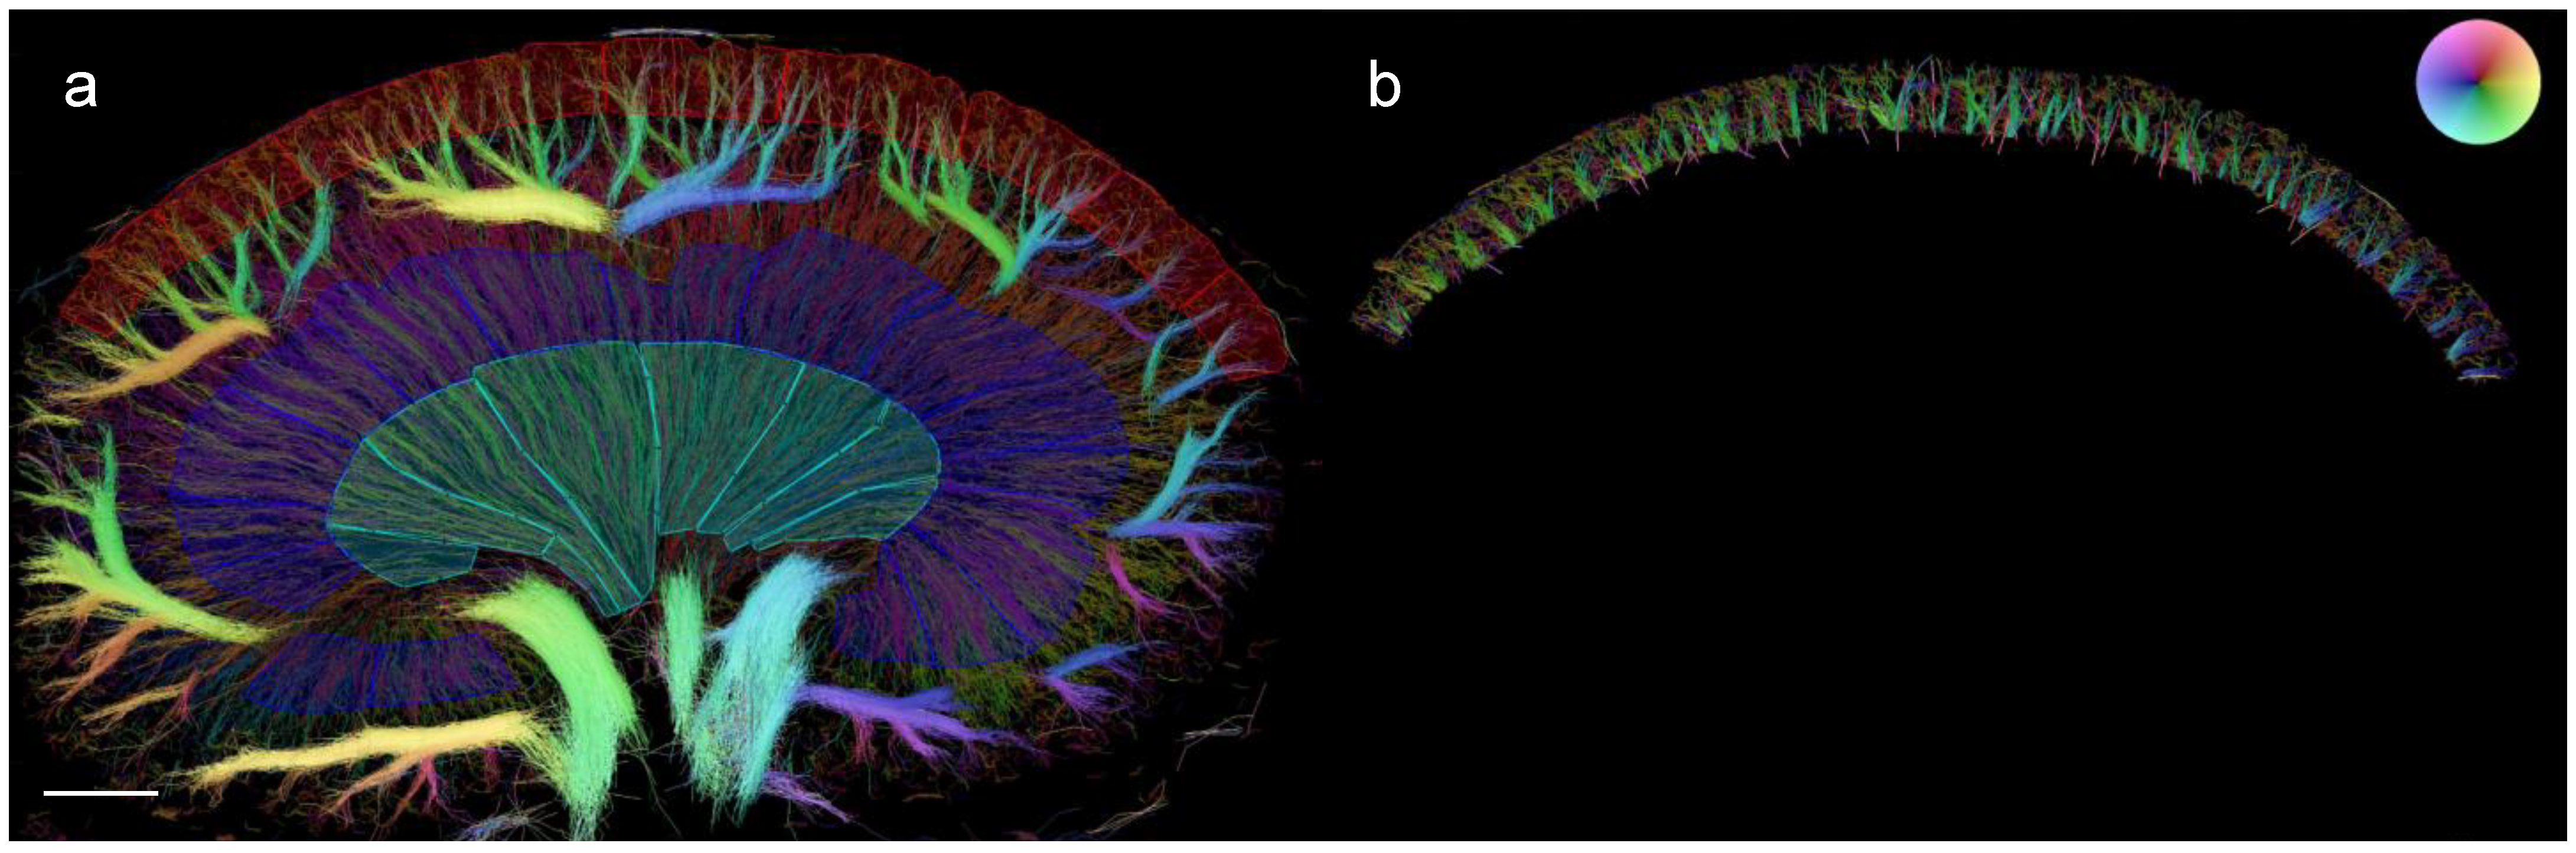

2.4. In Vivo Super-Resolution Ultrasound Imaging and Post-Processing

2.5. Ex Vivo µCT Imaging

- Andersen, S.B.; Taghavi, I.; Kjer, H.M.; Søgaard, S.B.; Gundlach, C.; Dahl, V.A.; Nielsen, M.B.; Dahl, A.B.; Jensen, J.A.; Sørensen, C.M. Evaluation of 2D Super-Resolution Ultrasound Imaging of the Rat Renal Vasculature Using Ex Vivo Micro-Computed Tomography. Sci. Rep. 2021, 11, 24335. [Google Scholar] [CrossRef] [PubMed]